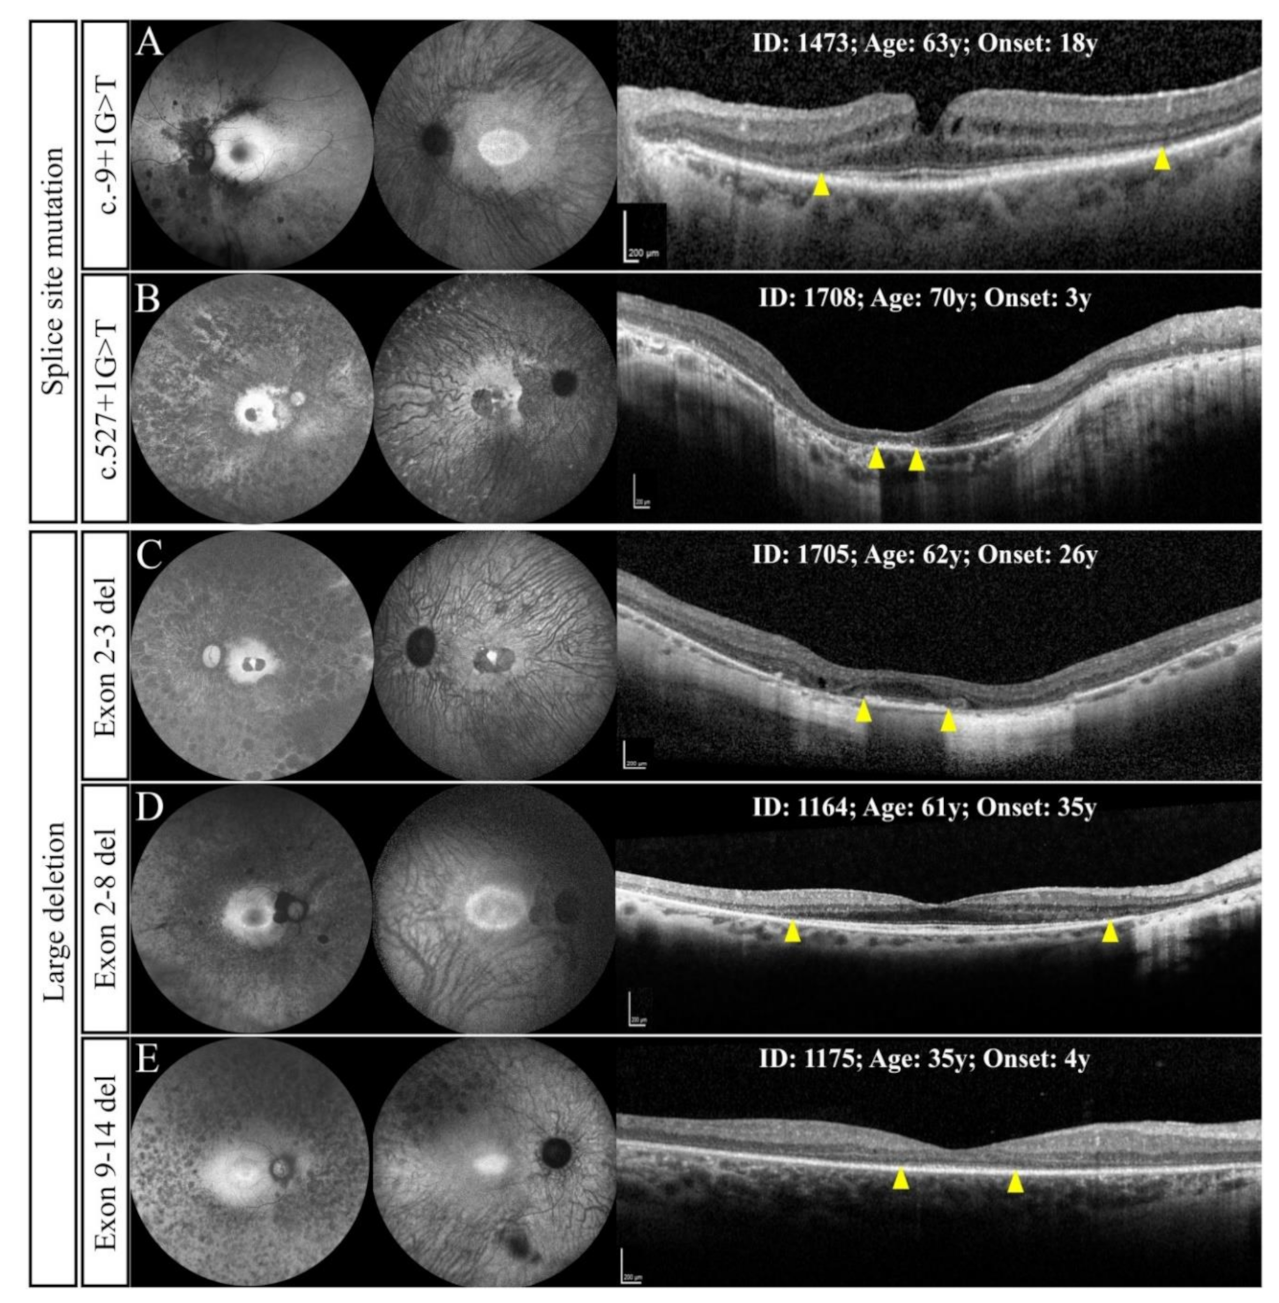

3.2.2. Splice Site Mutations

3.2.3. Large Deletions

| 0244 | 1473 | 63 | M | 18 | HM ‡ | 35 (20/200) | NSC + | NSC + | c.-9+1G>T | C |

| 2097 | 1708 | 70 | F | 3 | CF | CF | IOL (56) | IOL (56) | c.527+1G>T | A |

| 0213 | 1705 | 62 | F | 26 | 35 (20/200) | 64 (20/50) | IOL (56) | IOL (51) | Exon 2–3del | B |

| 0725 | 1164 | 61 | F | 35 | 70 (20/40) | 70 (20/40) | IOL (58) | IOL (58) | Exon 2–8del | C |

| 0155 | 1175 | 35 | M | 4 | 59 (20/63) | 64 (20/50) | PSCC + | PSCC + | Exon 9–14del | A |